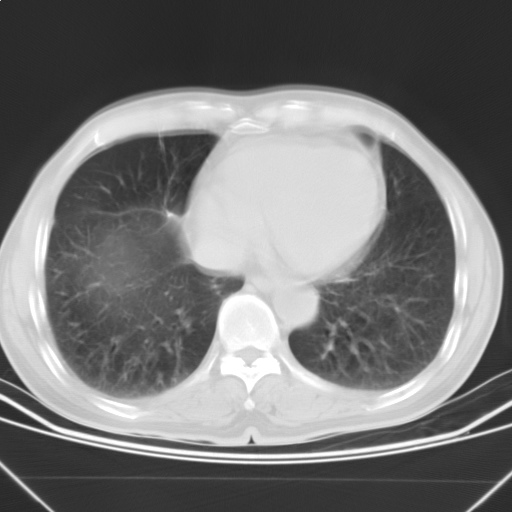

以下是引用随光逐影在2009-5-1 13:53:00的发言:[br]考虑为:1)两肺血行播散型肺结核;2)右肺下叶炎症感染。3)右侧胸膜增厚。